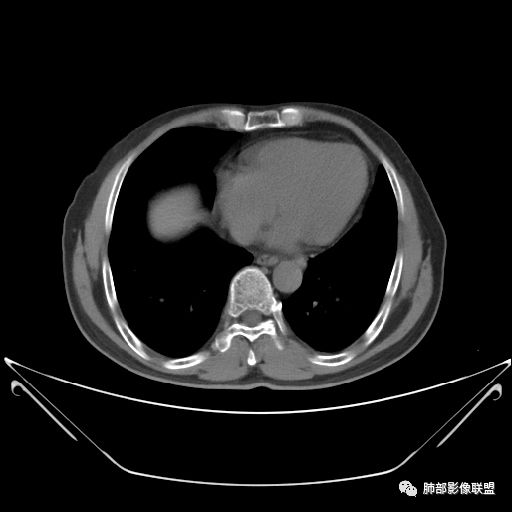

住院4天后行胸部增强CT

静脉期